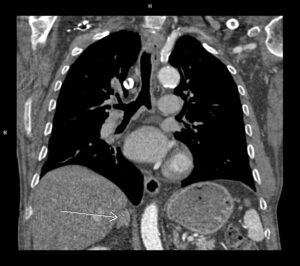

Figura 1: reconstrucţie oblic coronală aortă preoperator